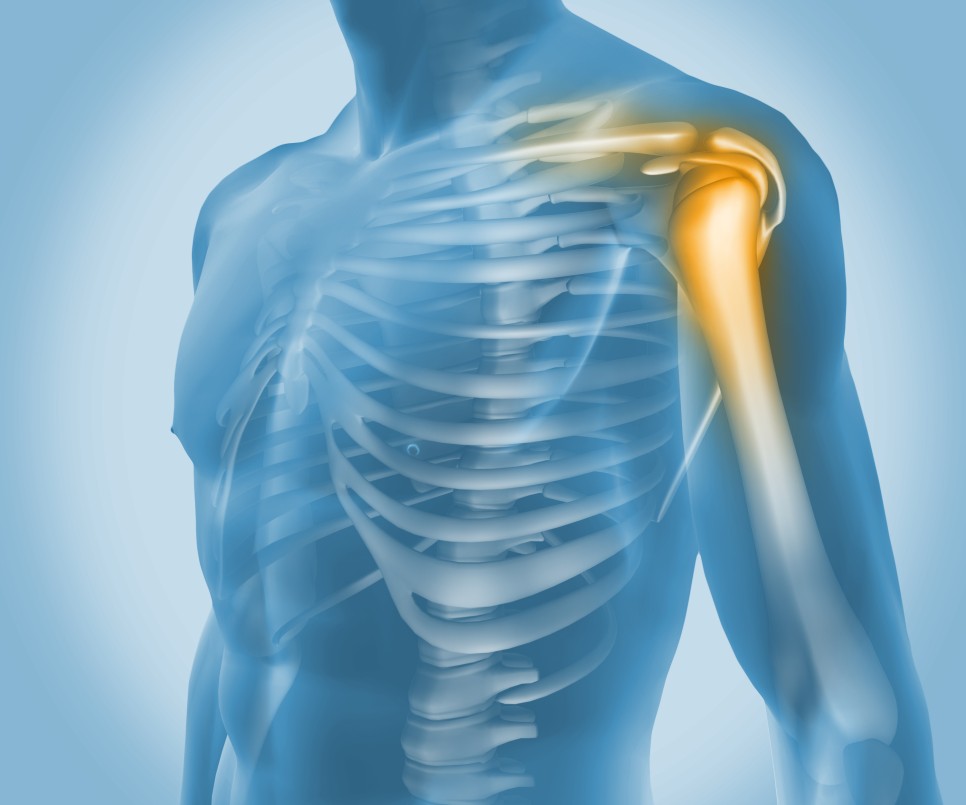

사람의 어깨에 석회가 생기는 병에 대해서 알고

계시나요? 이 병을 우리는 흔히 '석회성건염'이라

부르는데요. 다양한 관절 부위에 나타날 수 있지만

특히 어깨 회전근의 힘줄 부위에 석회가 침착되는

일이 많다고 합니다.